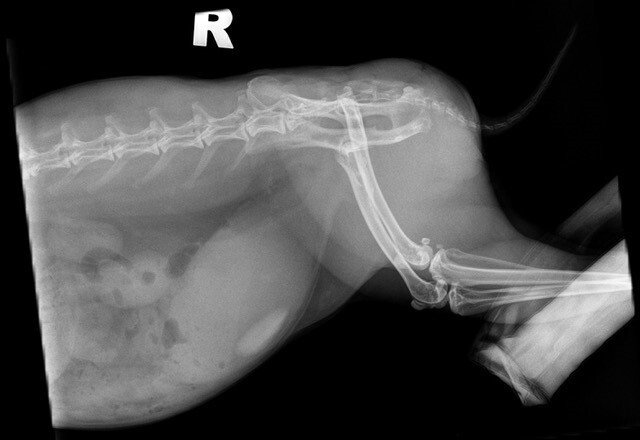

Because the majority of uroliths in guinea pigs are composed of calcium carbonate, radiographs are ideal to assess for uroliths within the urinary tract (Figure 4). Radiographs are especially important to assess for any smaller uroliths within the urethra if a larger stone is identified within the bladder lumen.